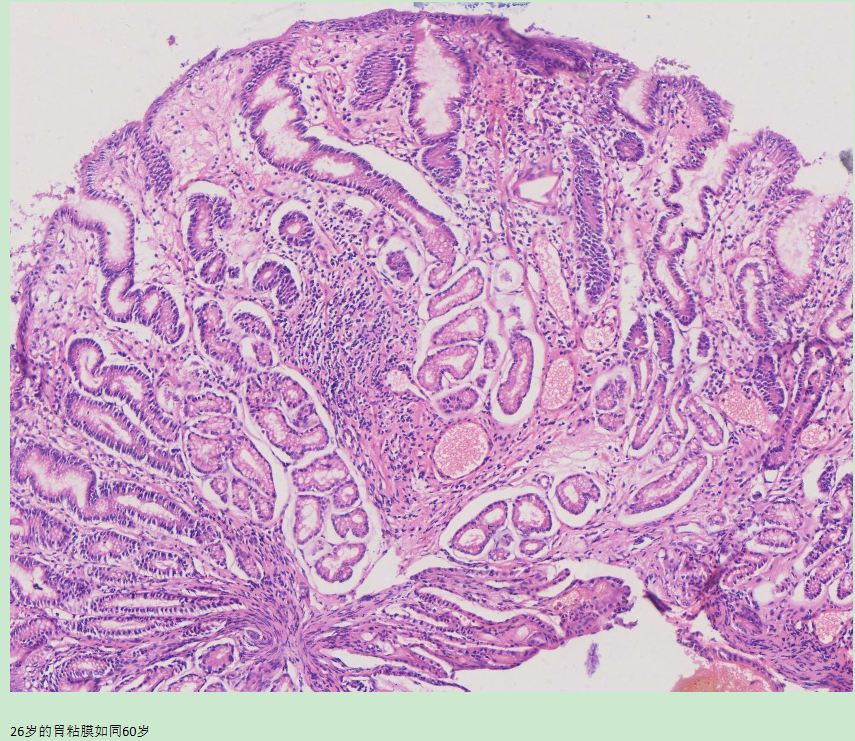

当我们在深入观察人体的胃部(胃镜+病理)后,一定会发现胃龄在不断变化之中。有的人虽然60岁了,胃粘膜却如同30岁的人;反之,有的人只有30岁,胃却到了60岁。可见,胃龄是不与实际年龄同步的。一旦胃早早“衰老”了,对身体各个部件的影响也就会接踵而至。

如何判断自己的胃龄是目前医学还没有很好解决的课题。直接的证据是胃镜观察+活检病理组织学。两者结合起来,判断胃龄就准确多了。